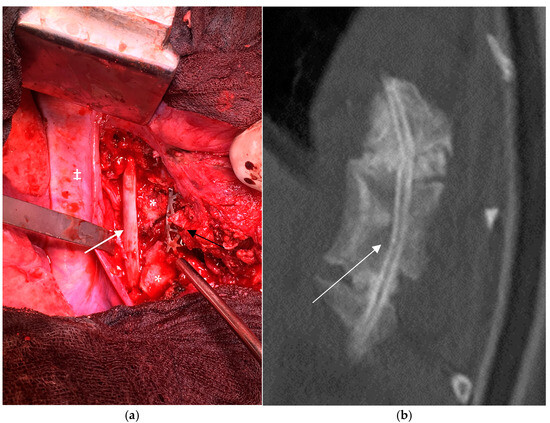

3.3.1. Anterior Spinal Fusion

3.3.6. Bone Grafting

4. Results